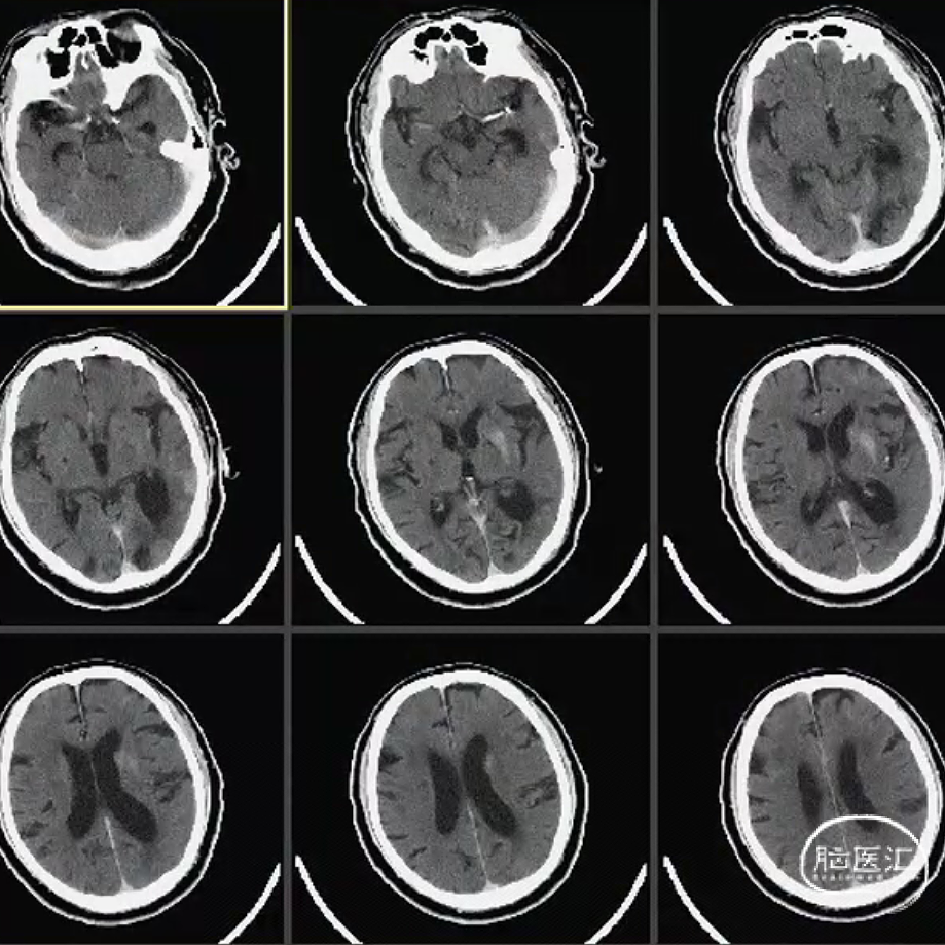

术前CT

术后CT少许造影剂渗出可能,24h复查较前吸收